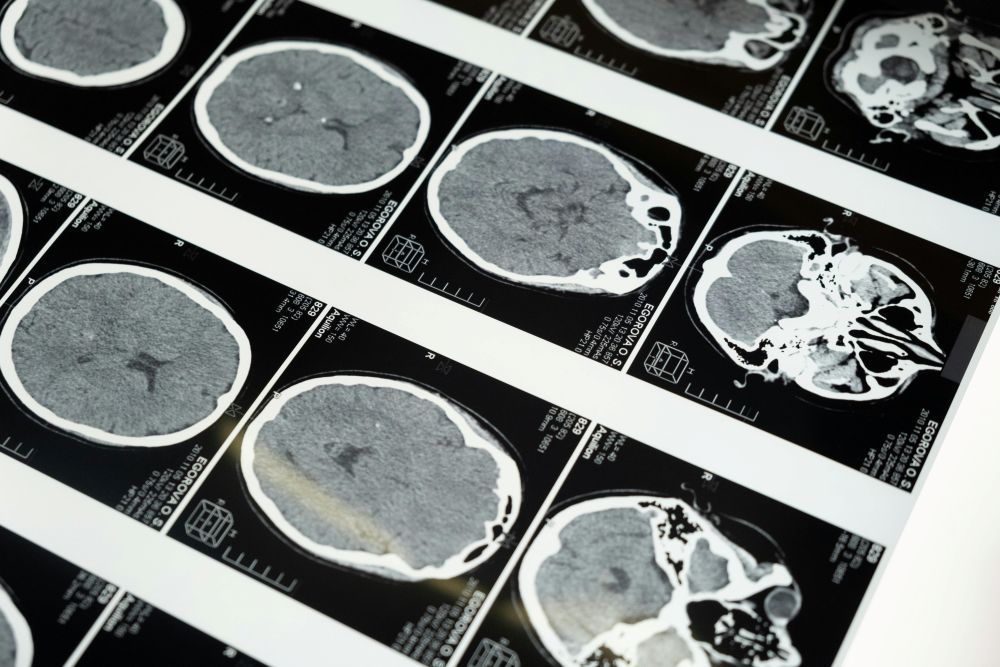

The latest research from teams at the University of Maryland School of Medicine and several partner sites has drawn attention because it suggests a new way to help people living with glioblastoma, the most aggressive type of brain cancer. In a trial that included 34 patients, doctors used MRI-guided focused ultrasound before giving standard chemotherapy. Patients who received this added step lived noticeably longer than a large group of similar patients who received only standard treatment. While the sample was small, the results were strong enough that many in the field are watching closely.

Every patient in the trial had already undergone surgery to remove as much of the tumor as possible. In glioblastoma, surgery is only part of the process because tiny cancer cells almost always remain. After surgery, patients usually start chemotherapy and radiation. In this study, some patients also had focused ultrasound treatments spaced out over several months. This technique temporarily opens the blood-brain barrier, a natural protective shield that blocks many substances—including most medicine—from entering the brain. The barrier is helpful for preventing infection but makes treating brain cancer extremely difficult.